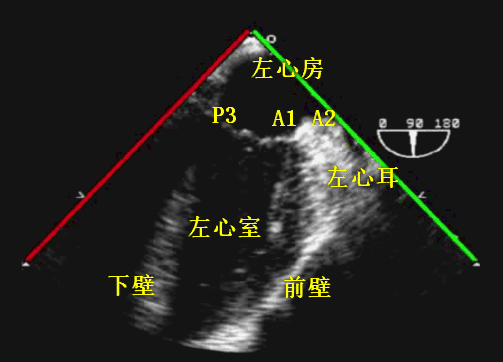

超声探头位置与前述四腔心切面时一致、位于左心房后部,旋转晶片角度至 90° 左右,此时右心房及右心室便从图像中消失,左心耳出现。并同时后屈探头、加大超声视野深度,可显示整个心尖部。该切面与四腔心切面相垂直,左室前壁位于图像右侧、左室下壁位于图像左侧(图 12)。

根据二尖瓣的解剖分区,该探查切面会经过二尖瓣 A1、A2、P3 等部分(图 13)。此切面主要用于评估二尖瓣病变、测量二尖瓣瓣环尺寸、诊断左心耳占位、测量左心室大小及功能等。